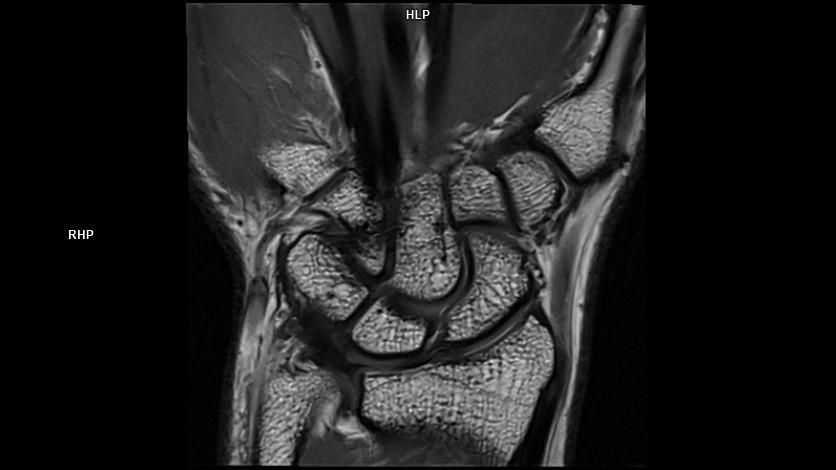

Coronal PD DR Sharp-MAGNETOM Lumina

07/07/2021

Coronal PD DR Sharp-MAGNETOM Lumina/Coil-Special Purpose/Resolution-448/Scan Time-2:22